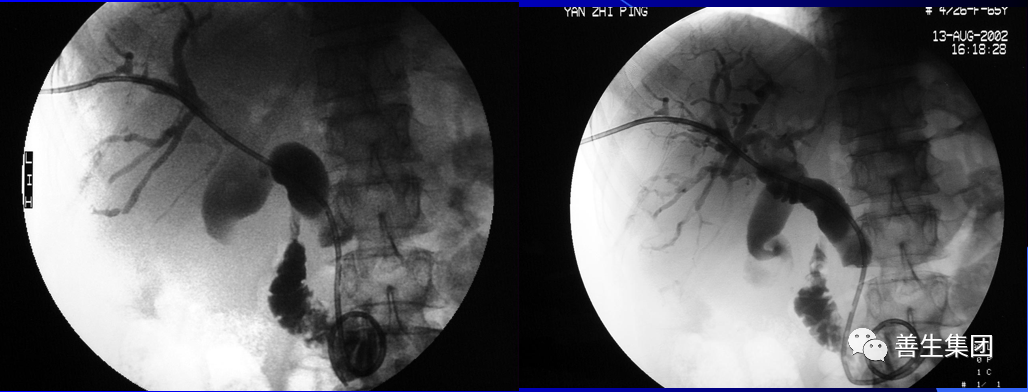

PTC示左右肝管内间广泛充盈缺损,为胆道出血正像

胆管支架什么样子经皮肝胆管穿刺置管引流术(PTCD)及胆道内支架临床应用_https://www.jmylbn.com_新闻资讯_第5张

胆管支架什么样子经皮肝胆管穿刺置管引流术(PTCD)及胆道内支架临床应用_https://www.jmylbn.com_新闻资讯_第6张

胆管支架什么样子经皮肝胆管穿刺置管引流术(PTCD)及胆道内支架临床应用_https://www.jmylbn.com_新闻资讯_第7张

胆管支架什么样子经皮肝胆管穿刺置管引流术(PTCD)及胆道内支架临床应用_https://www.jmylbn.com_新闻资讯_第8张